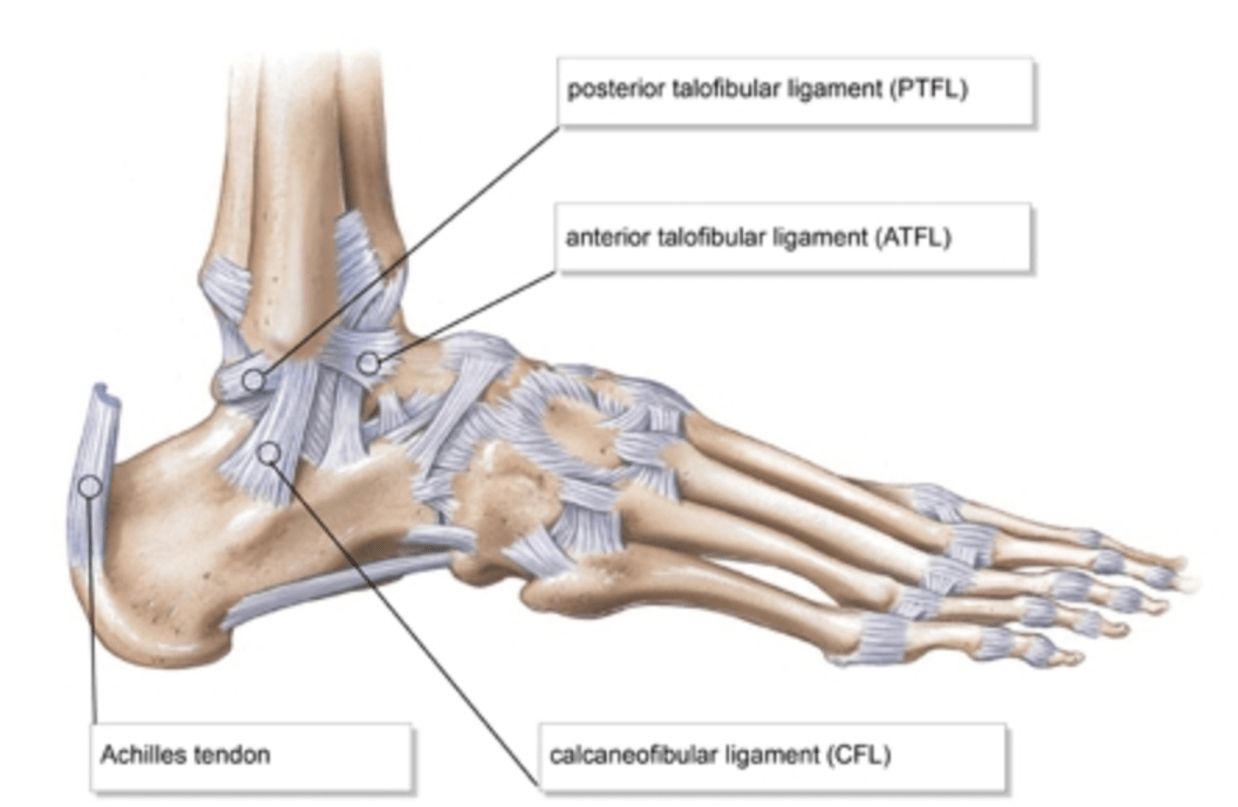

What are the lateral stabilizers of the ankle

What is the most commonly injured ligament in the foot

What is Anterior Talofibular Ligament (ATFL)?

Which ligaments are injured in type II supination ankle sprain

What is ATFL and CFL?